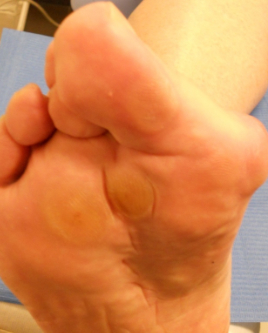

Metatarsalgia

Metatarsalgia: antes Metatarsalgia: después